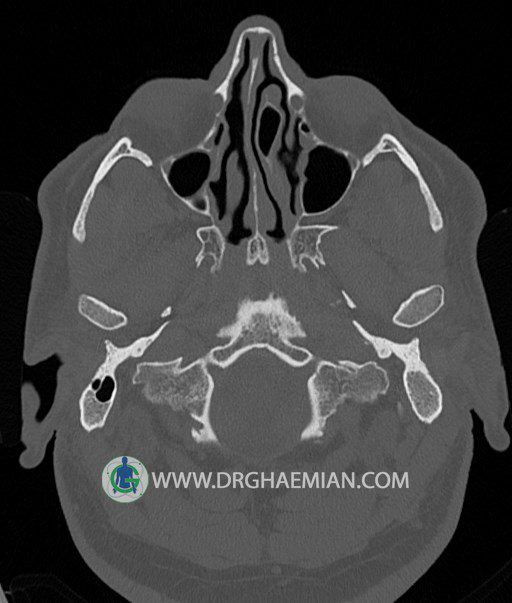

سی تی اسکن گوش داخلی به رادیولوژیست اجازه می دهد تا سطوح مختلف، یا اسلایس هایی از استخوان های که از جمجه به گوش می روند را از طریق امواج ایکس چرخشی مشاهده کند. در این کیس اودیت مدیا، ماستوئیدیت مزمن، اوتیت خارجی، انحراف سپتوم بینی، کونکا بولوزا و افزایش ضخامت سینوس ها مشاهده می شود.

گزارش پزشک :

در HRCT از استخوان تمپورال با مقاطع آگزيال ، ساژيتال و کرونال ظريف ( 0.6 mm ) :

– نماي کوکلهآي دو طرف با 2.5 دور گردش مجرا

– نماي cochlear aqueduct

– نماي semicircular canal خلفي ، لترال ، فوقاني و وستيبول

– استخوانچه هاي گوش داخلي شامل malleus ، incus و stapes (دنسيتي و رديف استخوانچه ها )

– نماي oval window و round window ، tympanic cavity ، attic و کانال گوش داخلي

– کانال عصب فاشيال و مسير ان از ناحيه کانال گوش داخلي ، geniculate ganglion تا محل خروج ان از stylomastoid foramen

– نماي tympanic membrane ، کانال ICA ، بولب جوگولار دو طرف

در حد طبيعي است .

– اپاسيتي گوش مياني چپ ناشي از وجود دانسيته نسج نرمي دراطراف استخوانچه ها همراه با اروژن اسکوتوم و

استخوانچه ها بدون جابجايي در رديف استخوانچه ها مشهود است که مطرح کننده اوتيت مديا همراه با نشانه

هاي مشکوک به کولستئاتوم مي باشد .

– اپاسيتي و اسکلروزيس ماستوئيد چپ نشانه ماستوئيديت مزمن

– اپاسيتي کانال گوش خارجي ناشي از دانسيتي نسج نرمي مطرح کننده external otitis

– انحراف سپتوم مياني بيني به راست

– کونکا بولوزا در کونکاي مياني چپ و

– افزايش ضخامت مخاطي در سينوس هاي اتموئيد و ماگزيلاري

اپاسيته